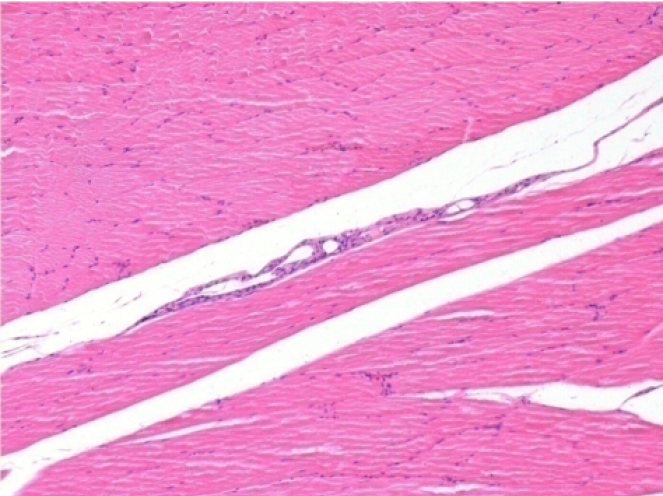

Endopeel Injection in Subcutaneous Tissue

0.5 ml ( 5x 0.1ml) Endopeel SC Injection in the right subcutaneous pretibial area.

L:200x-Control-SC

R-D10-SC-200X

R-D30-SC-200X

R-D90-SC-200X

R-D210-SC-200X

R-D210-SC-400X

- Endopeel induces a selective reversible myofibrolysis and inflammatory reaction on a period of 1 month, approximately

- Muscular changes are reversible in almost full totality

- The muscle is the better place to inject Endopeel because of more efficacity, control and duration of its action

- No necrosis nor abcess have been found all over the study.